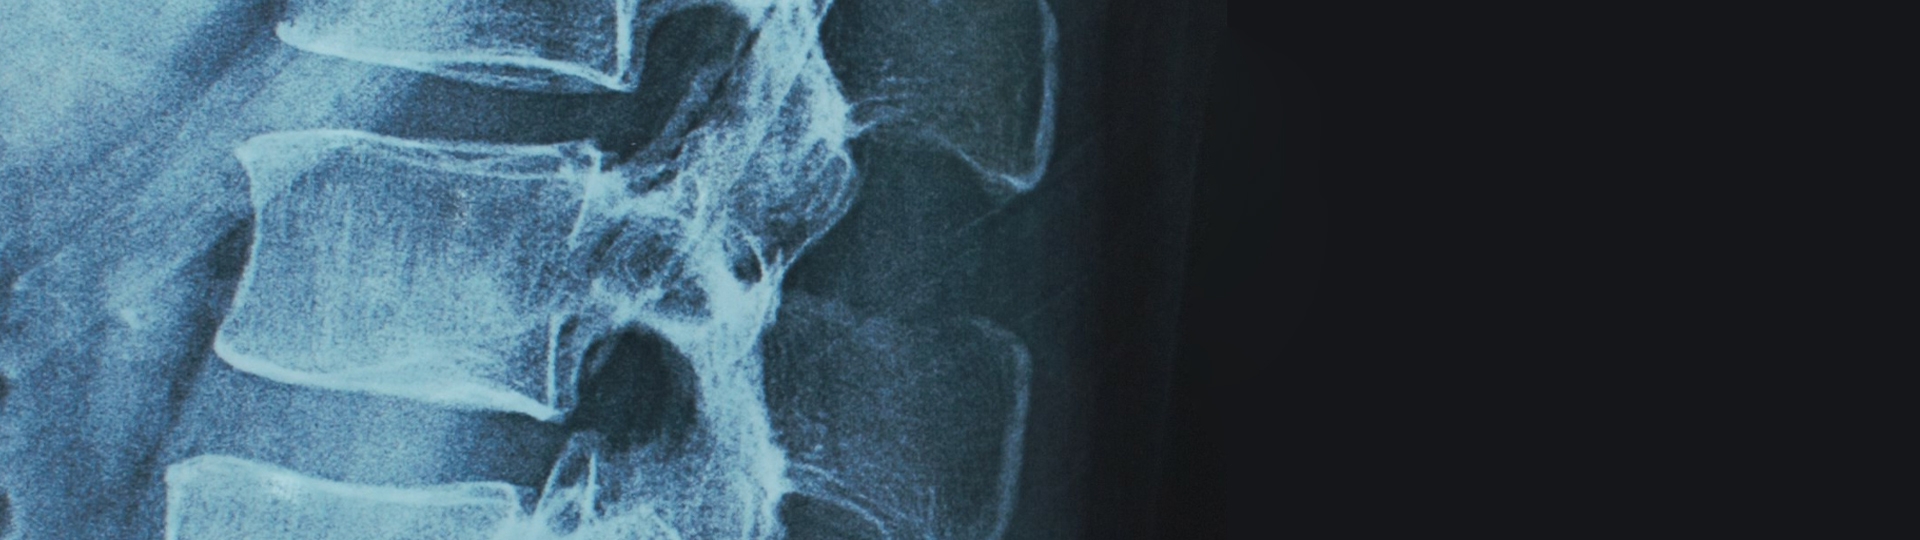

Neurosurgery is a medical specialty around the diagnosis and treatment of injury to, or diseases and/or disorders of the brain, spinal cord, spinal column and peripheral nerves.